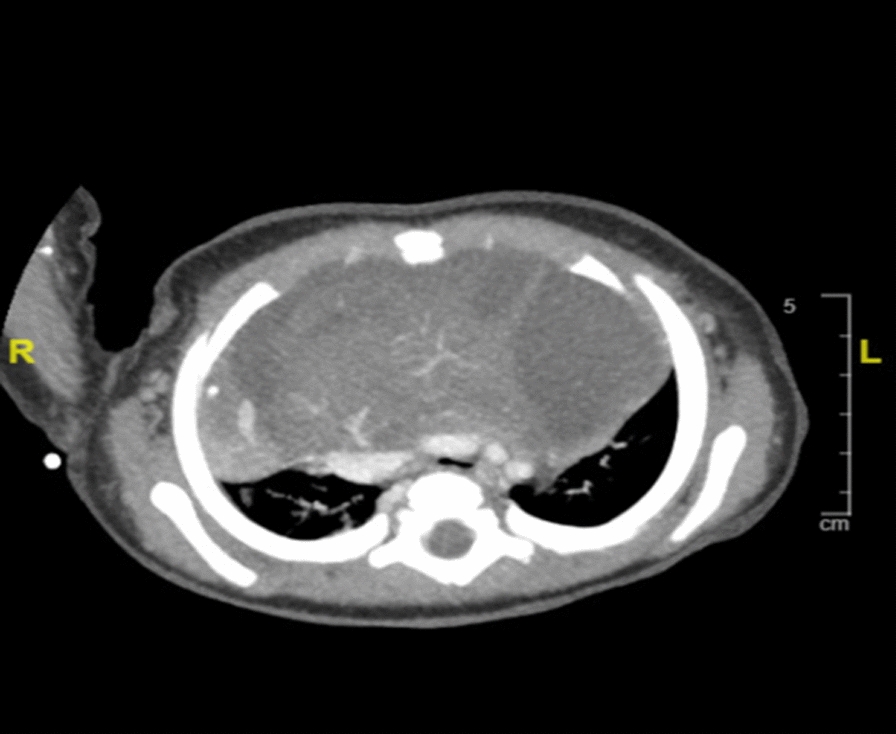

Here we present a 3-month-old Middle Eastern infant weighing 3.2 kg with a large congenital teratoma who presented to the emergency room with cyanosis and respiratory distress. During his hospital course, he underwent three procedures, two of them under light-to-moderate sedation: a diagnostic computer tomography scan followed by mass content drainage by interventional radiology (Figs. 1, 2). On the third day, he had a thoracotomy with complete tumor resection under general anesthesia with the help of an epidural for pain control (Fig. 3). The resected tumor weighed 2.5 kg, which was equal to twice the patient’s total body weight (Fig. 4). After the surgery, he was extubated in the operating room and discharged home 3 days later.

Fig. 2

Cross-section computed tomography (CT) showing large anterior mediastinal mass (AMM)